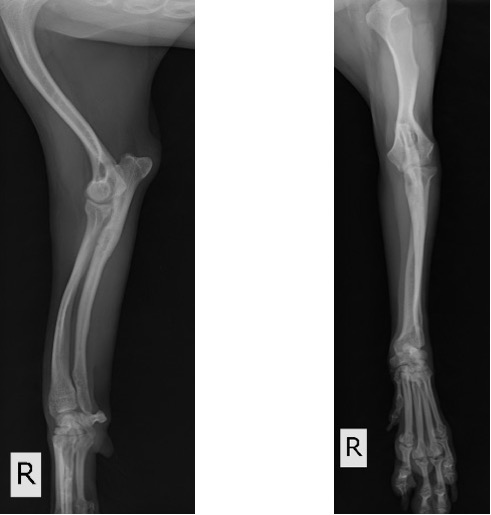

術後1ヵ月 (移植した骨が少しずつ癒合し始めてきましたが、K-wireの先端が軟部組織を刺激してしまっているためか、肘頭の腫脹が認められました。)

術後2ヵ月 (K-wireの先端が軟部組織を刺激し、患肢の着地を阻害していると考えられたため、抜ピンを実施しました。)

術後3ヵ月 (移植骨の癒合良好で、K-wireの刺入孔も不明瞭化してきました。)

術後6ヵ月 (骨切り線が完全に消失しました。)